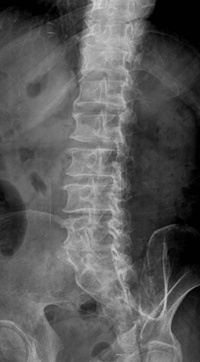

만약 나이가 50세 이상인데 허리통증이 발생했다면 허리디스크보다는 오히려 척추의 퇴행성 변화로 인한 척추관협착을 의심해 보는 것이 좋다.

척추관협착증은 척추 속 신경이 지나가는 척추관과 추간공이라는 공간이 척추뼈의 노화로 뼈와 황색인대가 퇴화되고 두꺼워져 신경이 지나가는 길, 즉 척추관이나 신경구멍이 좁아지기 시작하면서 신경을 압박하는 질환이다. 신경을 압박한다는 점에서 허리디스크와 같지만 허리디스크는 뼈 자체의 노화가 아니라 척추뼈 사이의 디스크가 돌출돼 생기는 것이라는 점에서 두 질환은 치료법에서부터 확연히 달라진다.

금천구에 위치한 척추전문 희명병원(이사장 최백희) 신경외과 전문의 진료부장 김정철 박사는 “척추협착증은 허리디스크와는 다르게 척추의 노화로 인해 나타나는 증상이기 때문에 시간을 지체하게 될수록 더욱 증상이 심해지게 되며, 하지마비나 대소변 장애 등이 나타날 수도 있습니다. 그렇기 때문에 빠른 시일 내에 치료를 받도록 해야 합니다” 라며 척추관협착증의 치료를 권하고 있다.

척추의 노화로 인한 퇴행성 질환인 척추관협착증의 경우에는 환자들 대부분이 고령층 환자이기 때문에 환자의 상태를 많이 고려해서 치료해야 한다 치료 초기에는 주사요법을 포함한 물리치료나 약물치료 같은 보존적인 치료를 우선적으로 시행한다. 그러나 6개월간의 보존적 치료에도 불구하고 환자의 통증이 계속되거나, 초기 증상임에도 극심한 통증을 호소하는 경우에는 환자의 상태와 나이 등을 고려하여 수술 여부 등을 결정해야만 한다.